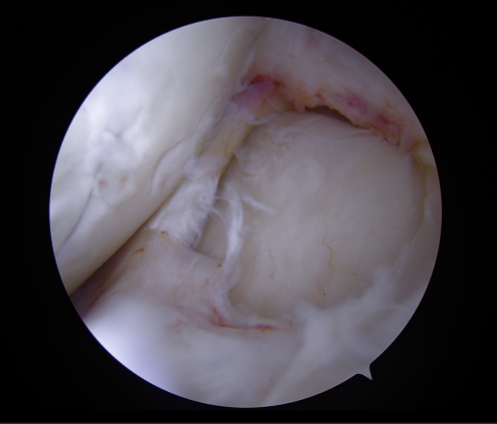

▶수술 전_관절내시경 사진 01

▶수술 전_관절내시경 사진 02

영상검사를 통해 확인한 소견은 비교적 명확했습니다.

- - 외측 대퇴골(LFC)에 발생한 거대 골연골박리(OCD, Osteochondral Defect)

- - 외측 반월상연골(Lateral Meniscus) 파열

- - 오른쪽 무릎의 외반 변형(Valgus knee)

특히 문제였던 것은 OCD 병변의 크기가 ‘Huge’ 수준이었다는 점입니다.

이 정도 크기의 병변은 휴식이나 주사치료 같은 보존적 치료만으로는 충분한 회복을 기대하기 어렵고,

치료 시기를 놓치면 연골 손상이 더 진행될 수 있습니다.